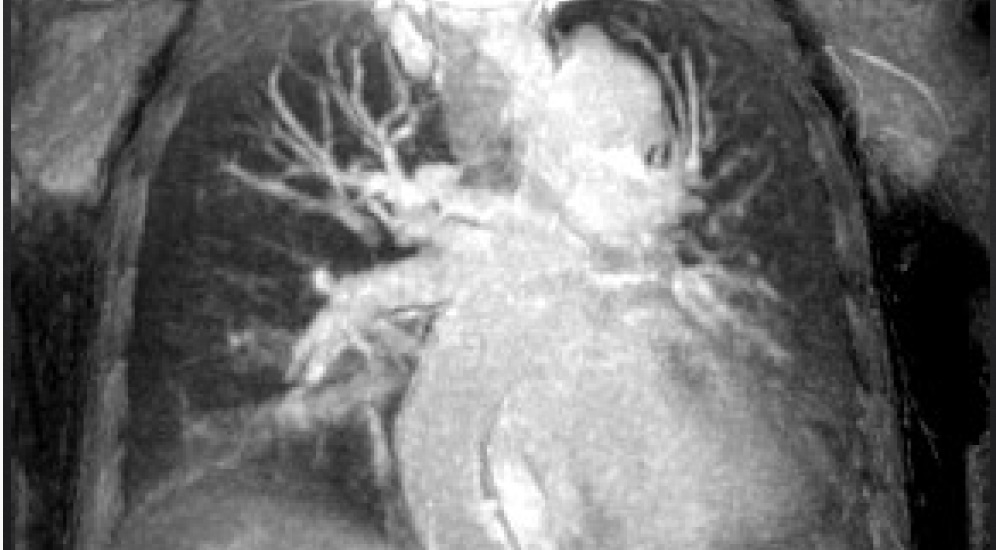

高分解能肺動静脈撮像

磁場の均一性が向上したことで、従来と比べて広範囲の部位を歪みのない画質で撮像することができます。さらに、AI技術を用いたノイズ低減と超解像技術を併用することで、従来と同じ解像度であれば大幅な検査時間の短縮を、従来と同じ時間であればより高解像度の画像を取得することが可能となりました。例えば、数分かかっていた全脳のT2強調画像が、救急診療時にはわずか5秒で撮像することができ、限られた時間で多くの情報を得ることができます。

12月中旬から運用が開始されたキヤノン社製「Vantage Galan 3T / Supreme Edition」は、心臓部にあたるマグネットや傾斜磁場システムを国産のものとした最新の3T MRI装置です。